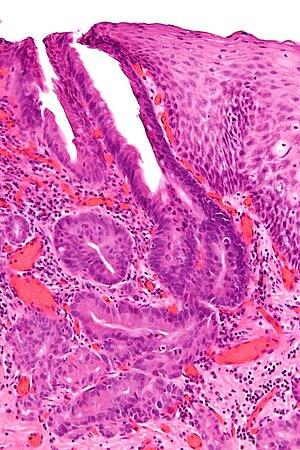

April is Bowel Cancer Awareness Month

Almost 4,000 people will be diagnosed with bowel or colorectal cancer (CRC) this year in Ireland. Most occur in adults over 60 years of age, but growing numbers of adults under 50 years are diagnosed

BY 2030, 10% OF COLON CANCERS AND 22% OF RECTAL CANCERS IN THE USA ARE EXPECTED TO BE DIAGNOSED IN PATIENTS YOUNGER THAN 50 YEARS.

Caught early CRC is treatable Access to diagnostics and screening saves lives. In Ireland, BowelScreen is available to adults 59-69 years. The US and Australia have dropped population screening to age 45+ Dr James O'Mahony, UCD School of Economics, presented compelling evidence for expansion of screening at the recent PriCAN meeting

Patient Patricia Stack, a UL graduate, and co-founder of the Irish early-onset CRC group recently called for pathways for early-onset CRC patients;

Access to diagnostics pathways to address the needs of people below 59 who are not met by the BowelScreen program

GPs education and awareness on the rise of earlyonset Colorectal Cancer so symptomatic patients are not dismissed as being too young Guidelines and Diagnostic Options for GPs (GP Guidelines) for Early Onset Colorectal Cancer

THE MARIE KEATING FOUNDATION IS CALLING ON OUR GOVERNMENT TO REDUCE THE AGE FOR BOWEL CANCER SCREENING FROM 59 TO 50.